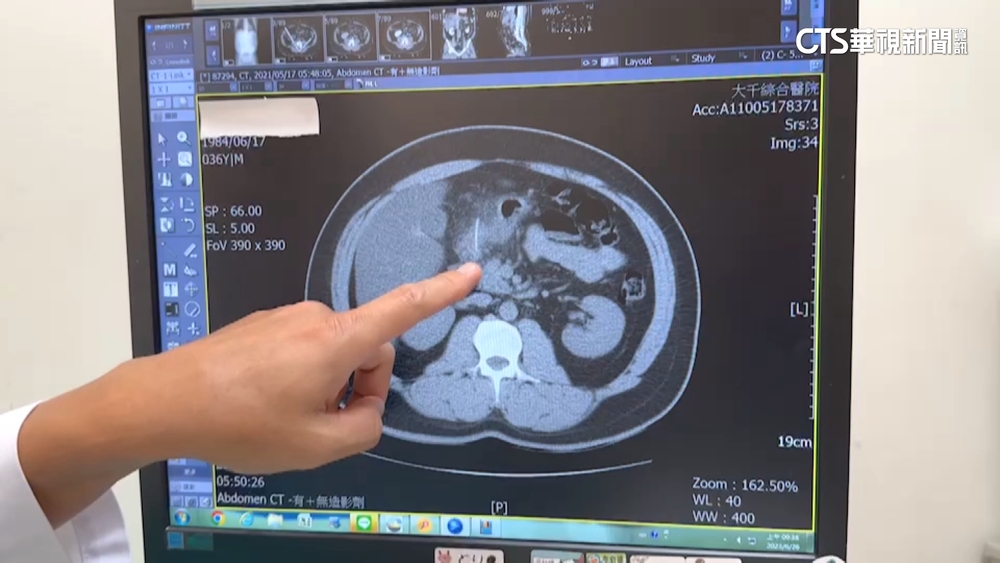

4公分魚刺「卡十二指腸」 男腹膜炎險敗血性休克